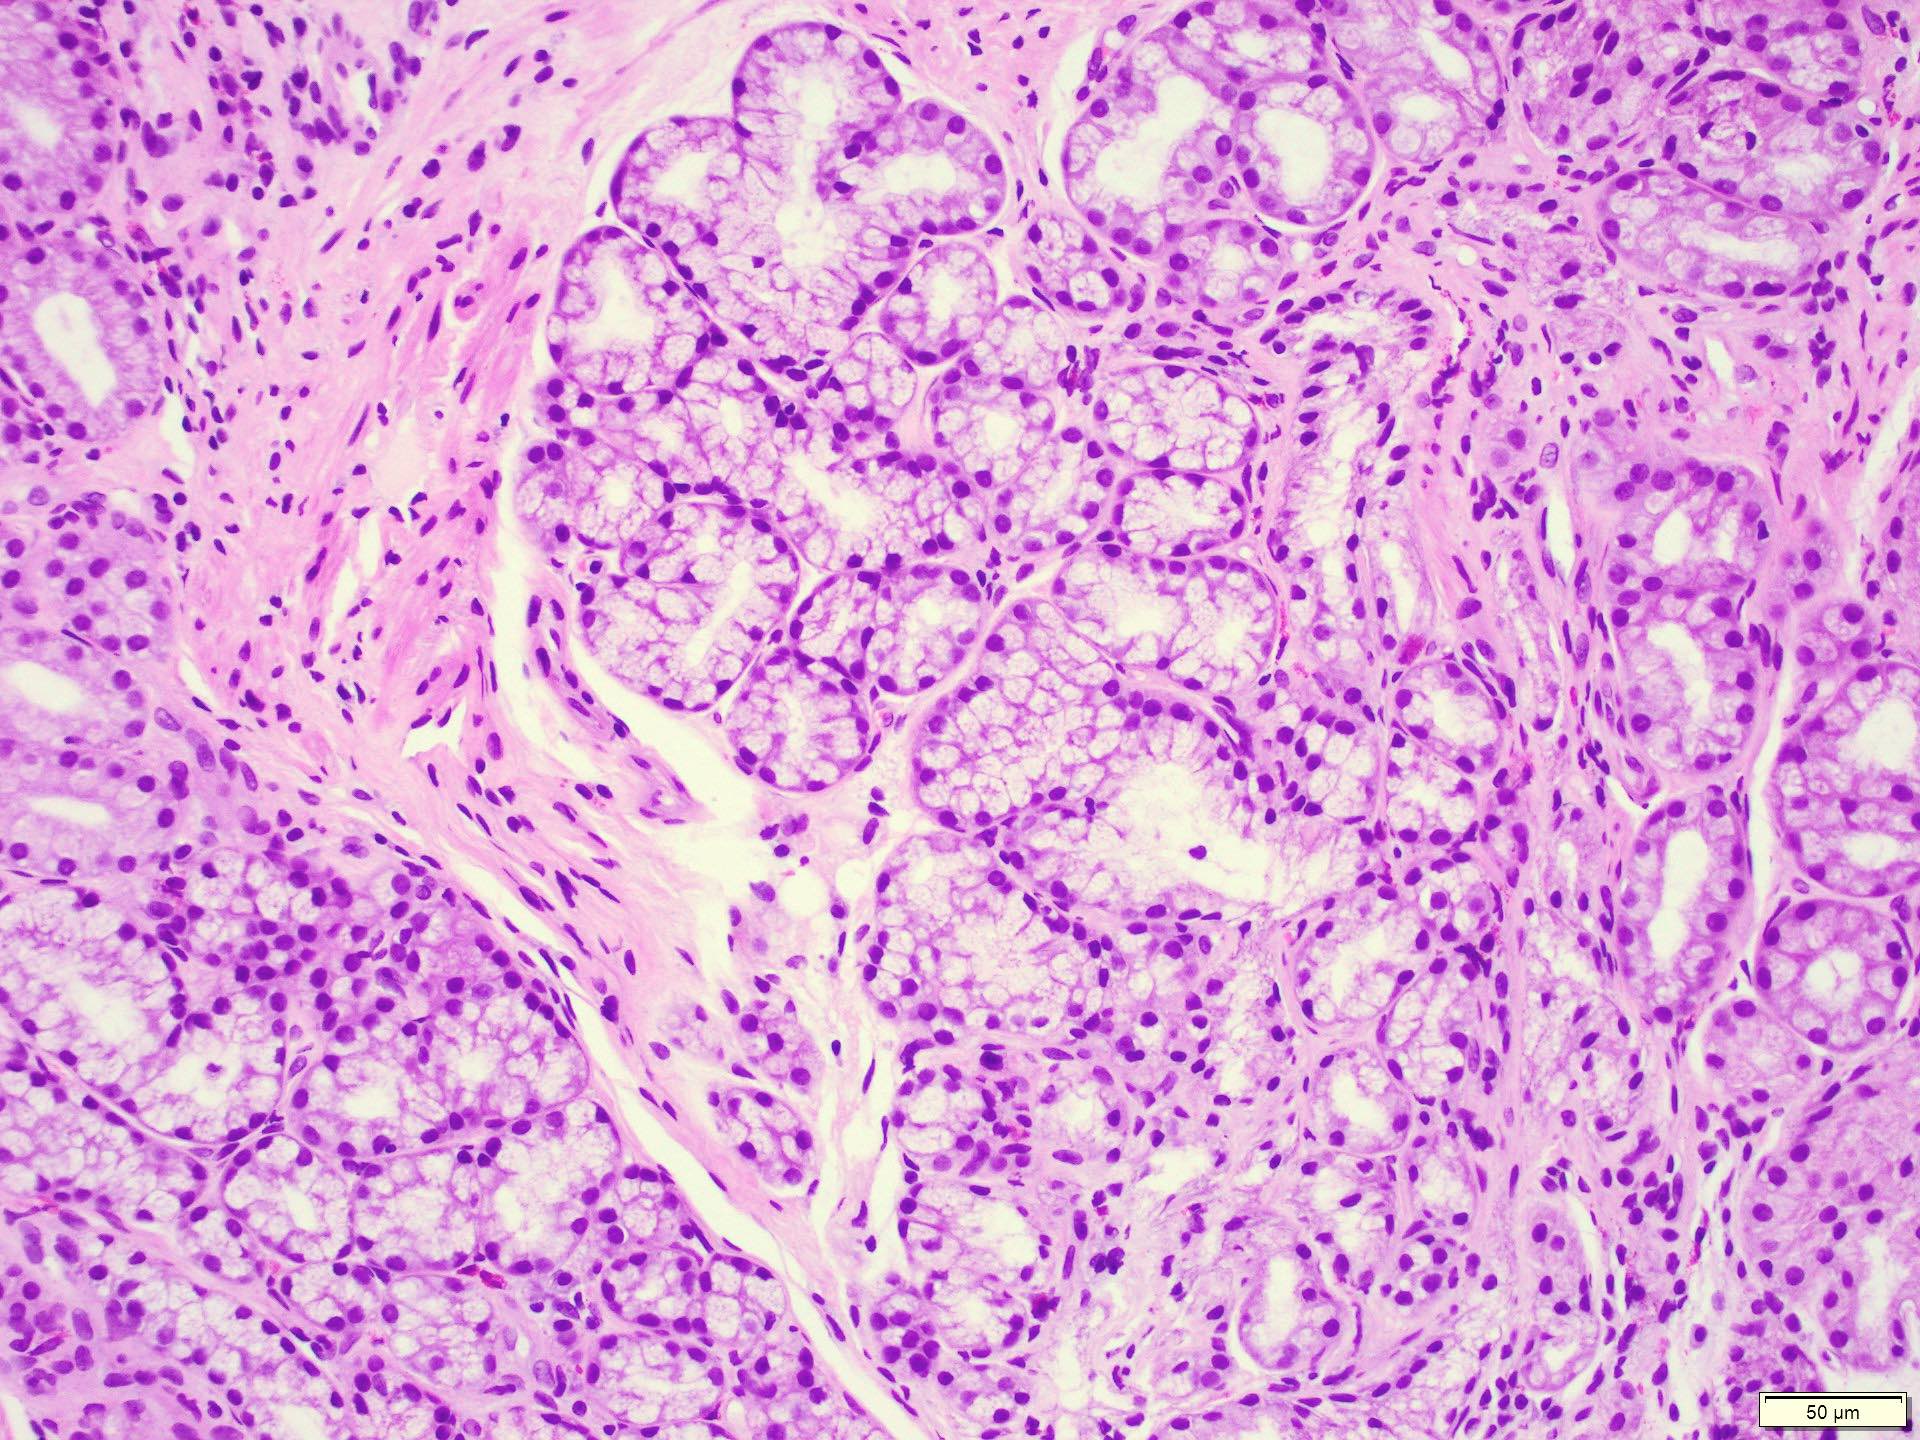

Product Name: Brunner glands in stomach store

Description store, Histology at SIU store, Brunner s glands Wikipedia store, Brunner s glands Wikipedia store, Brunner s gland store, Description store, Histology at SIU store, Brunner s Glands Vital Digestive Secretions CHOQ store, Brunner s gland hamartoma and hyperplasia store, Brunner s glands are found in the submucosa of the duodenum but store, Dictionary Normal Duodenum The Human Protein Atlas store, Histology at SIU store, Brunner s gland hyperplasia was found on histopathology from a store, Description store, Webpathology A Collection of Surgical Pathology Images store, Brunner Gland an overview ScienceDirect Topics store, Surgical management of giant Brunner s gland hamartoma case store, Pathology Outlines Brunner gland hyperplasia store, Description store, Brunner s Gland Hyperplasia A Rare Cause Of Gastric Outlet store, Pathology Outlines Brunner gland hyperplasia store, Brunner s gland YouTube store, Figure 2 from Brunner s Gland Hyperplasia A Rare Cause Of Gastric store, Brunner s Gland Hamartoma Over Treatment of a Voluminous Mass store, brunner s glands secrete a bicarbonate buffer to regulate pH of store, Saving from unnecessary pancreaticoduodenectomy. Brunner s gland store, Gastric outlet obstruction caused by Brunner s gland hyperplasia store, Underlying risk factors of Brunner s gland hamartoma Download store, A giant Brunner s gland hamartoma being treated as a pedunculated store, Figure 2 from Brunner s gland hyperplasia an unusual cause of store, Block10 1 Fig 9. 93W4522 Stomach and Duodenum ls H E store, Brunner s Gland Hyperplasia and Hamartoma Imaging Features with store, Medbullets Brunner s glands are found only in the Facebook store, Clinics and Practice Free Full Text Multiple Adenocarcinomas store, Pathology Outlines Brunner gland hyperplasia store, Brunner glands Radiology Reference Article Radiopaedia store, Brunner s Gland Hyperplasia and Adenoma Associated with Colic in store, Match the following Gland Location 1. Brunner s gland i Stomach store, Ileum is characterised by the presence ofa Brunner s glands and store, Webpathology A Collection of Surgical Pathology Images store, Histology at SIU store, INSIGHTS INTO THE DEVELOPMENT OF GASTROINTESTINAL BRUNNER S GLANDS store, Figure 3 from Gastric Outlet Obstruction Caused by a Triple Lesion store, Brunner s Gland Hyperplasia and Hamartoma Imaging Features with store, Pathology Outlines Brunner gland hyperplasia store, Brunner s Glands Hyperplasia Diagnosis with EUS F store, Full Text Large Brunner s Gland Hamartoma A Case Report store, brunner glands Diagram Quizlet store, Brunner Gland Hamartomas Uncommon Presentations and Endoscopic store, Duodenal Ulcer II The Gastrointestinal Atlas store.

Brunner glands in stomach store